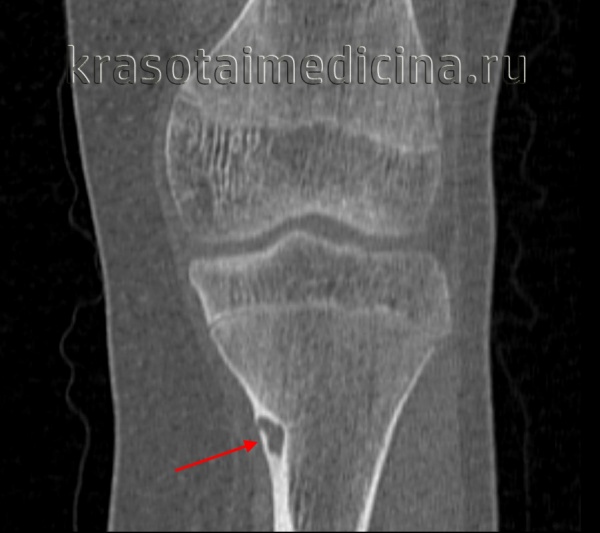

Рентгенограмма остеоид-остеомы проксимального отдела бедра. Имеется рентген-прозрачное образование с четкими контурами, окруженное склерозированной костью. Размеры прозрачного участка всегда меньше 1,5 см. Рентгенограмма голени в прямой проекции: остеоид-остеома малоберцовой кости. Обратите внимание на доброкачественный характер реакции кортикального слоя и увеличение объема кости. Остеоид-остеома диафиза бедра. Обратите внимание на утолщение кортикального слоя кости и доброкачественное периостальное новообразование костной ткани. Еще одним характерным признаком заболевания является интрамедуллярный склероз (стрелка). После рентгенографии методом выбора для диагностики остеоид-остеом является КТ, — очень чувствительный метод обнаружения при интра- и юкстакортикальном расположении «гнезда». Такое поражение сопровождается значительным утолщением кортикального слоя. Обратите внимание на случайное близкое расположение питающей артерии. Очень чувствительным методом диагностики остеоид-остеом является сцинтиграфия костей. В данном случае отмечается значительное усиление сигнала от пораженных дистальных отделов бедренных костей. Аксиальный КТ-срез (а) и взвешенный по Т2 МР-скан (б) с типичными признаками юкстакортикальной остеоид-остеомы дистального отдела бедра. На КТ виден типичный медуллярный склероз вокруг образования. На МРТ—выраженный сопутствующий отек костного мозга и периостальная реакция прилежащей надкостницы. Отечность проксимальной фаланги указательного пальца вследствие остеоид-остеомы. Интраоперационная картина «гнезда». Макропрепарат. «Гнездо» обычно имеет вишневокрасную окраску. При микроскопическом исследовании видны тонкие, хаотично расположенные остеоидные трабекулы, между трабекулами располагается богатая сосудами рыхлая соединительная ткань. При большем увеличении в веществе остеоида видны одинакового вида остеобласты без атипии ядер.

(Слева) Рентгенография в боковой проекции: кортикально-диафизарная ОО с выраженным утолщением заднего кортикального слоя большеберцовой кости. Утолщенная кость скрывает собственно гнездо опухоли

(Справа) КТ, аксиальная проекция, без контрастного усиления: у этого же пациента визуализируется задняя периостальная реакция в виде нагромождения, окружающая округлый литический очаг, глубоко погруженный в кортикальный слой. Эта ОО располагается непосредственно около питающего сосуда. Такое взаимоотношение наблюдается часто. (Слева) Рентгенография в боковой проекции: овальный литический очаг и окружающая его зона склероза В, которые позволяют диагностировать ОО.

(Слева) КТ, корональная проекция, костный режим: интрамедуллярная ОО таранной кости. Обратите внимание на склерозированное гнездо опухоли, окруженное кольцом просветления, что характерно для такого типа ОО. Окружающая зона склероза отсутствует. Расположение в кистях/стопах является типичным.

- Рентгенография кости. На снимках визуализируется кистообразные изменения или неоплазия в виде «мыльных пузырей» в метафизарной зоне. Признаки общего остеопороза отсутствуют, вокруг измененного участка может просматриваться остеосклероз. Границы доброкачественной ГКО более четкие, но из-за местно-агрессивного роста при значительном размере возможно появление «костного козырька». Выраженная периостальная реакция нехарактерна. Злокачественная остеокластома имеет нечеткую структуру. На снимках рано обнаруживается разрушение кортикального слоя.

Опухоль кости, состоящая из остеоида, а также незрелой костной ткани. Характерны малые размеры, хорошо заметная зона реактивного костеобразования и четкие границы. Чаще выявляется у молодых мужчин и локализуется в трубчатых костях нижних конечностей, реже – в области плечевых костей, таза, костей запястья и фаланг пальцев. Как правило, проявляется резкими болями, в отдельных случаях возможно бессимптомное течение. На рентгенограммах выявляется в виде овального или округлого дефекта с четкими контурами, окруженного зоной склерозированной ткани. Лечение – резекция вместе с очагом склероза. Прогноз благоприятный.